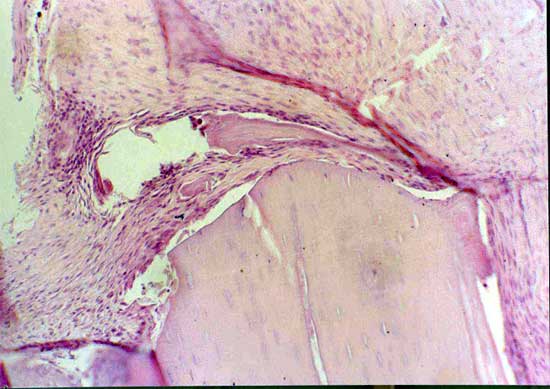

2周软骨岛                              骨断端无骨痂

4周软骨钙化                            骨小梁形成

髓腔形成                              X线4周(BM vs MSC)